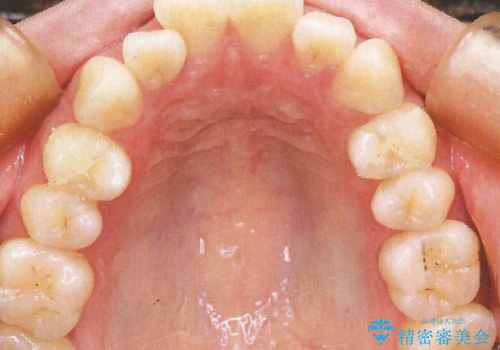

- リンガルブラケット

上顎の前から4番目の歯を両側抜歯して、上下裏側の装置で前歯を引っ込める計画としました。

裏側からの矯正であったため、表側に比べて少し治療期間を要しました。